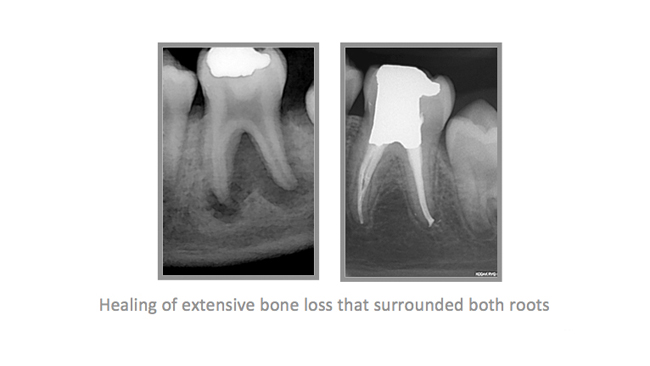

• A few Teeth Treated by Dr. Katsarsky

• A few Cases Treated by Dr. Katsarsky